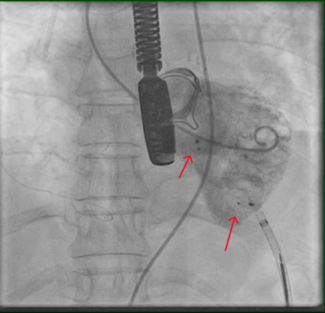

Coronary and graft angiography was performed via left transradial approach. Native coronary angiography revealed left coronary dominance with significant obstruction of the left main coronary artery by a single discrete lesion. The LAD and circumflex arteries were patent but diseased, with the occluded first obtuse marginal branch being supplied by a patent saphenous vein graft. Notably, competitive flow was present in the mid-LAD due to filling from both the proximal native vessel and LIMA graft (Figure 1, Video 1).

Coronary and graft angiography was performed via left transradial approach. Native coronary angiography revealed left coronary dominance with significant obstruction of the left main coronary artery by a single discrete lesion. The LAD and circumflex arteries were patent but diseased, with the occluded first obtuse marginal branch being supplied by a patent saphenous vein graft. Notably, competitive flow was present in the mid-LAD due to filling from both the proximal native vessel and LIMA graft (Figure 1, Video 1).

Based upon competitive flow noted during native vessel angiography, internal mammary graft patency was expected. Surprisingly, the LIMA was found to be proximally occluded (Figure 2). To reconcile the apparent discrepancy, exploration was performed for alternate sources of LAD filling. It was found that the LIMA downstream of the occluded origin filled via a single branch arising directly from the ipsilateral thyrocervical trunk (Figure 3, Video 2). The etiology of the proximal LIMA occlusion remains uncertain, but conceivably could have been related to vessel injury during coronary artery surgery. Regardless, an initial conservative strategy was felt appropriate, with the possibility of percutaneous intervention (native vessel or graft), or repeat CABG in the future, if required.

Based upon competitive flow noted during native vessel angiography, internal mammary graft patency was expected. Surprisingly, the LIMA was found to be proximally occluded (Figure 2). To reconcile the apparent discrepancy, exploration was performed for alternate sources of LAD filling. It was found that the LIMA downstream of the occluded origin filled via a single branch arising directly from the ipsilateral thyrocervical trunk (Figure 3, Video 2). The etiology of the proximal LIMA occlusion remains uncertain, but conceivably could have been related to vessel injury during coronary artery surgery. Regardless, an initial conservative strategy was felt appropriate, with the possibility of percutaneous intervention (native vessel or graft), or repeat CABG in the future, if required.